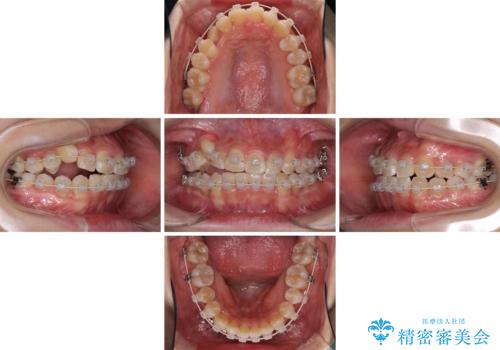

- 前歯のでこぼこと乳歯が残るほどの八重歯を気にして来院された患者様です。

非抜歯にてワイヤー矯正にて治療することとしました。(ただし、親知らずと乳歯は抜歯)

犬歯は歯根が太く長いため、移動には時間を要します。しかし、犬歯は機能面から考えて残すことを選択したいため、長期間をかけて治療を行うこととしました。